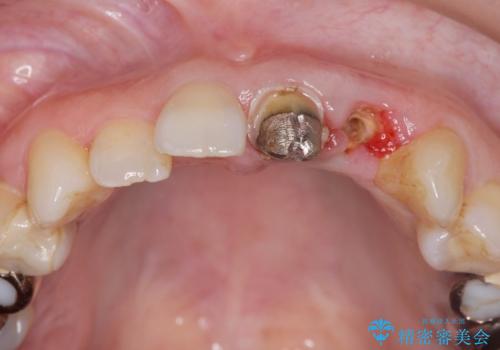

- 前歯がクラグラして噛めないことの改善を求めて来院されました。

X線撮影や歯周組織検査から、クラウン下の虫歯の再発や歯の破折が疑われる状況でした。

左上2は、クラウン メタルコアの除去を行ったところ虫歯の再発や亀裂を認め、長期的な予後の期待が難しいことから抜歯を行い

ブリッジで審美性の回復を行っていく運びとなりました。